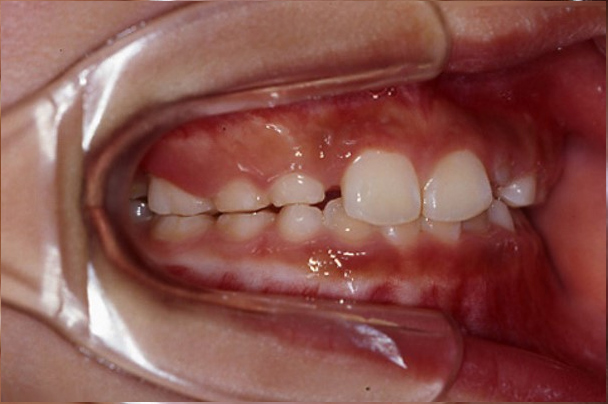

14歳6か月の男子|実例写真あり

上下顎歯列叢生の治療「マルチブラケット装置」で治療した症例

- 主訴:上の前歯のすき間が気になる。

- 診断名:上顎前歯の空隙歯列(すきっ歯)

- 治療に用いた装置:セクショナルアーチ(マルチブラケット装置の前歯のみ版)